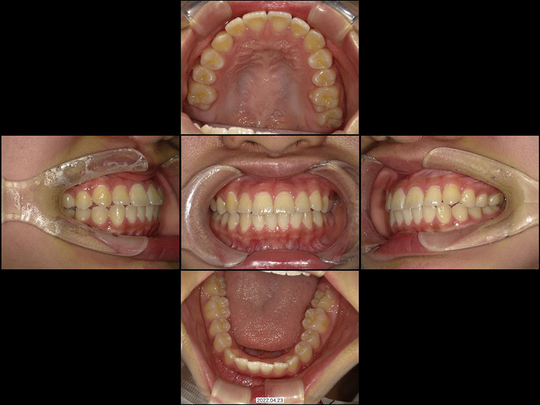

Mさん 10代 女性

矯正前

画像をクリックで拡大

矯正後

治療の説明

マウスピース型矯正装置を使った矯正治療にて全体矯正しました。抜歯することなく治療を終えています。

治療の期間・回数

1年8か月、12回

​費用

877,800円